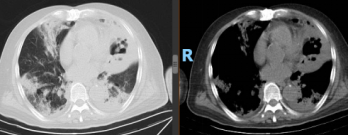

患者治疗10天后,复查炎症指标和胸部CT。

胸部CT复查结果: 双肺多发团片影,左肺内病灶可见空洞形成,双侧胸腔积液。